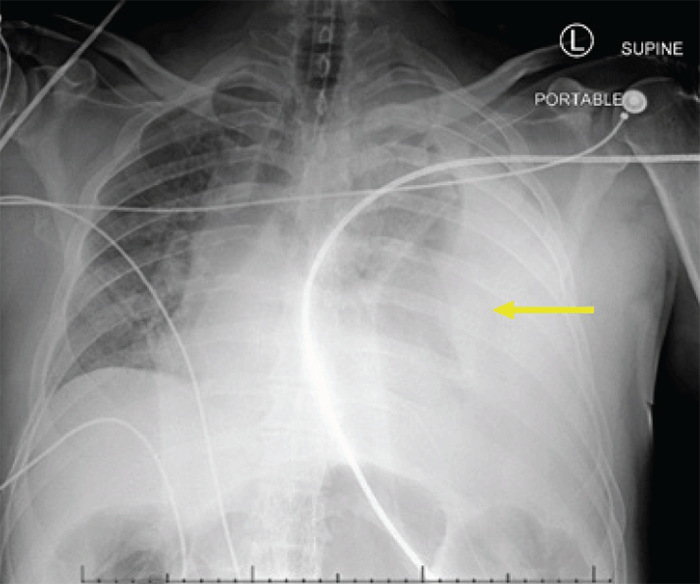

In the early morning hours of postoperative day 3, he complained of increasing left chest pain and received oral analgesics. He had an increasing sinus tachycardia from 77 bpm to 110 bpm. Several minutes after going to the bedside commode, he had a pre-syncopal episode and was helped back to his bed. He subsequently lost consciousness; immediate vital signs demonstrated a systolic blood pressure of 60 mmHg and a heart rate of 55 bpm. His skin was ashen and diaphoretic. He was given epinephrine with an improvement of his hemodynamics, and he regained consciousness. He immediately complained of bilateral leg paralysis. Anesthesia was called for emergent intubation. He was given a 1 L crystalloid bolus, received 200 μg  of phenylephrine, and started on a phenylephrine drip, rapidly titrated to 150 mcg/hour. An electrocardiogram demonstrated sinus tachycardia, labs were unremarkable, and a chest radiograph revealed a large left pleural effusion with a rightward displacement of his mediastinum and trachea (Figure 1). A tube thoracostomy was inserted into his left chest, immediately evacuating approximately 1400 ml of frank blood. His hemodynamic instability resolved within minutes. Aggressive balanced blood product resuscitation was initiated.

Figure 1. Large Left Pleural Effusion with Rightward Displacement and Compression of Mediastinum. Published with Permission